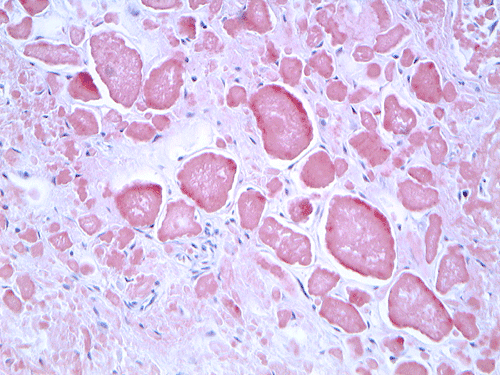

On low magnification, the mucosa appear intact and unremarkable. However, the submosa and muscular layer is replaced by a pale eosinophilic, hypocellular, amorphous material (Panel A). These material separate the smooth muscle bundles (Panel B and C). On Masson's trichrome, these material appears blue (Panel D). They are negative for elastic stain (Panel E). These material are stained orange by Congo Red stain (Panel  F and G) which gives an apple green birefrigence on polarized light (Panel H). Electron microscopy was performed and revealed non-branhing straight fibrils ranging from 6.6 to 8.3 nm in diameter consistent with amyloid.

Amyloid can be detected on routine hematoxylin and eosin (H&E) slides, all forms of amyloid deposits are amorphous and homogenous, with pale eosinophilic areas 15. Microscopic characterization of amyloid by special studies is necessary to confirm diagnosis of amyloidosis. Congo red histochemical stain remains gold standard for diagnosis and characterize by common to all amyloid aggregates orange or red color on light microscopy and clear apple-green birefringence under polarised light 1, 2. Most of the other stains available are not recommended to be used alone and are listed with decreasing specificity and sensitivity: Sirius red, thioflavine T, thioflavine S, toluidine blue, p-dimethylaminobenzaldehyde-nitrite, alcian blue, and crystal violet 15. Electron microscopy studies indicate that the basic assembled unit is a thin filament of about 4 nm in diameter, and that the mature fibrils consist of a few such proto-filaments aligned in parallel, often with a twist 2. Some other authors describe amyloid filaments under electron microscope as loose meshwork of 7–10 nm wide rigid, non-branching, hollow fibrils of indeterminate length. The fibrils measure from 30 to more than 1000 nm in length and are usually found in aggregates in extracellular spaces 15, 16.